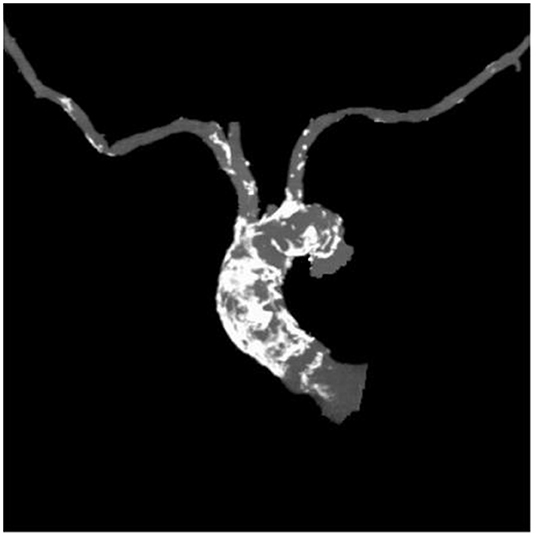

Table 1 outlines all baseline characteristics for the 56 patients. The patients were 29 (51.7%) male and 27 (48.3%) female, who were 74±15 years old (range 62 −89). The mean logistic EuroSCORE was 10.17%, the mean Society of Thoracic Surgeons score was 3.22%. One third of the patients were categorized as class III or IV of the New York Heart Association (NYHA). Almost half of the patients had concomitant coronary artery disease (48.2%). Myocardial revascularization was previously performed in 46.3% (PCI in 16%, CABG in 30.3%). 7.1% of patients had carotid disease, while 14.2% of patients had lower extremity artery disease. As such, 12% of patients needed to undergo a surgical cut as a vascular approach due to the nature of the disease (mainly heavy classifications). One patient also had severe stenosis of the popliteal artery. Lung disease was found in 25%, chronic kidney disease was present in 14.2% patients (i.e., one patient was on hemodialysis). The presence of porcelain aorta was considered to be direct indication for a TAVI in 14.2% of patients (Figure 2). TAVI was suggested to 2 patients due to chest deformation and previous chest irradiation. The mean left ventricle ejection fraction was 44% (range 15–65%), while the mean of the aortic pressure gradient was 45 mmHg (range 29–106 mmHg). The average aortic valve area was 0.58 cm2 (range 0.4–0.9 cm2).

Figure 2

Porcelain aorta.